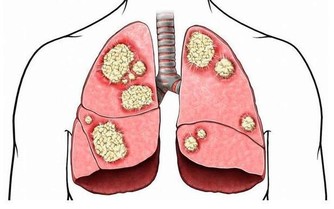

額頭痘反應出心臟和肺人們經常會說「腦門大的人聰明」,這裡說的「腦門」也就是我們的額頭,在中醫里將人體的部位分為上、中、下三焦,在《難經‧三十一難》中對上焦有記載:「上焦者,在心下,下膈,在胃上口」,而上焦的主要功能在與其主要功能是敷布水谷精氣至全身,以溫養肌膚、骨節,而額頭部位是反映心臟和肺的狀態,而額頭部位長痘,是上焦機能下降的表現,而心臟和肺都歸於上焦,所以若肺部太熱揮著心臟出現了異常的情況,在額頭或是眉宇間都會出現異常,而長痘就是常見的一種表現方式,正如《靈樞‧決氣》中所說:「上焦開發,宣五穀味,熏膚,充身,澤毛,若霧露之溉,是謂氣」。